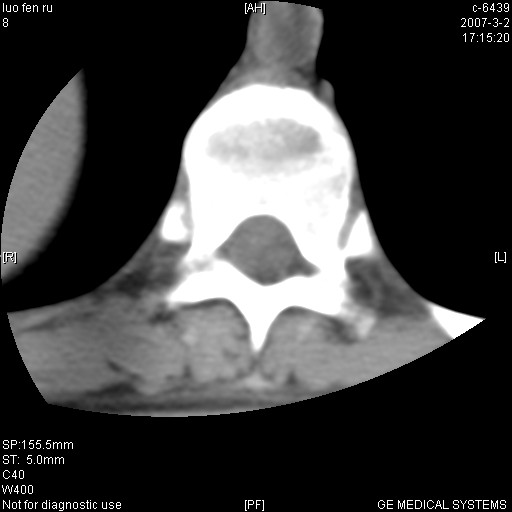

标题: CT6952:T11椎体病变请讨论

女,19岁.背部疼痛一月余.自诉幼时有个外伤史.

腰椎平片示,t11椎体呈楔形改变,椎间隙未见异常.

病人病史不长,病变表现比较明显,如果是结核,病史不支持,椎间隙不窄,临近椎体正常,椎旁无冷浓疡,但从病变本身硬化也较多,均不太支持结核。慎重考虑的话,可以问一下病人有无结核病史。如果没有,更多的应该考虑陈旧性骨折,伴有慢性椎间盘炎可能。确诊后记着告知啊!

t11椎体前缘不规则形骨质破坏,周围有硬化边,软组织肿块不明显,首先考虑:骨嗜酸性肉芽肿 。期待随访结果。